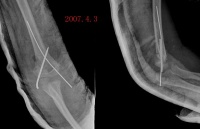

x线特征:受伤后不久可出现局限性肿快。伤后3-4周,在肿快内显示毛状致密象,其临近骨将显示骨膜反应。伤后6-8周,病变边缘部清楚地被致密骨质所包绕,而具有新生骨的外貌。软组织肿块的核心部有时显囊性变且逐渐扩大其内腔,到晚期而显出类似蛋壳状的囊肿。伤后5-6个月肿块收缩,因而肿块与邻近的骨皮质和骨膜反应之间显出x线透亮带。

1早期(反应期):

局部软组织出现肿块,有时发热,伴有疼痛,关节活动受限。X线摄片示软组织内有不规则棉絮状模糊或关节周围云雾状的钙化阴影,以肘关节骨化性肌炎为例,在前臂伸屈肌、肱二头肌及肱三头肌近肘关节处采用轻柔适中的抚、摸、揉、推、弹、拨等手法。以松解剥离肌腱、腱膜及肌肉的粘连,其后术者一手持患肢腕部,一手持肘关节上中部,轻微持续牵引。再持患肢腕部轻柔地做肘关节无痛下的内收,外展和前后屈伸方向的抖动及环转手法,切忌手法粗暴及对局部肿块和关节囊行按摩刺激。